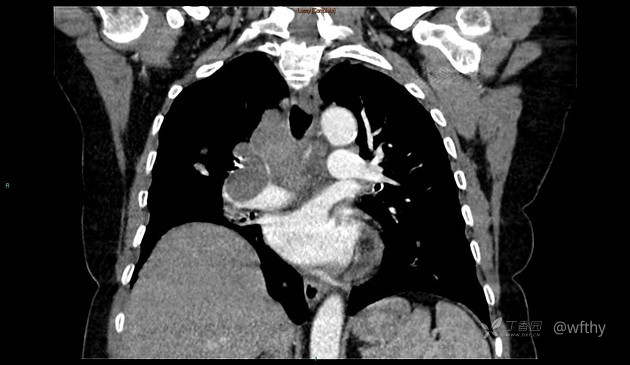

病例女65,头部肿块